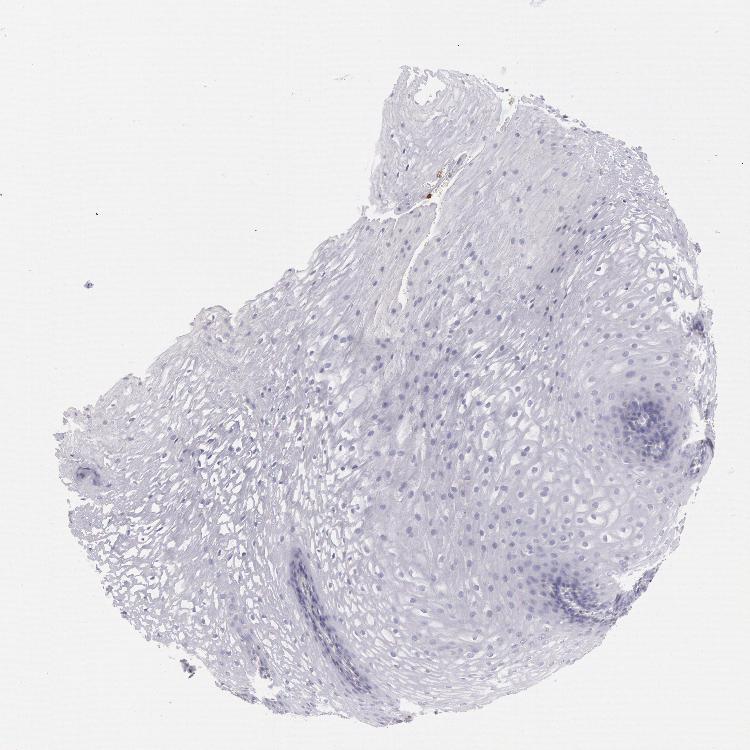

ESOPHAGUS - Antibody stainingi

Antibody staining in the annotated cell types in the current human tissue is reported as not detected, low, medium, or high, based on conventional immunohistochemistry profiling in selected tissues. This score is based on the combination of the staining intensity and fraction of stained cells.

Each image is clickable and will lead to virtual microscopy that enables deeper exploration of all samples and also displays staining intensity scores, fraction scores and subcellular localization as well as patient and tissue information for each sample.

Antibody HPA001333Antibody CAB034046

Squamous epithelial cells Not detectedNot detected